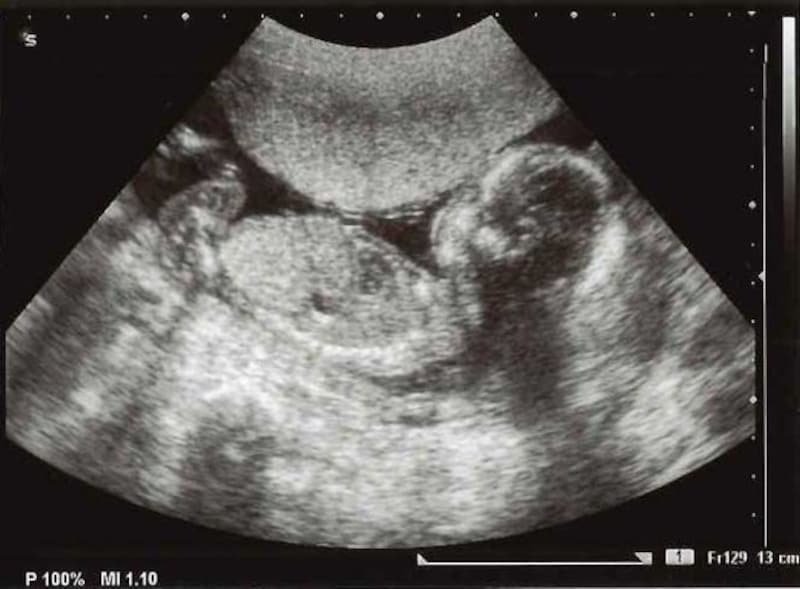

妊娠16週 赤ちゃんの性別が分かる人も!胎児の大きさ・エコー写真

妊娠17週目エコー写真・胎児の大きさ・胎動や性別が分かることも!

妊娠18週目エコー写真・赤ちゃんの大きさ・胎動が分かる人も

妊娠19週目 胎動や性別が分かる人も!胎児のエコー写真・大きさ